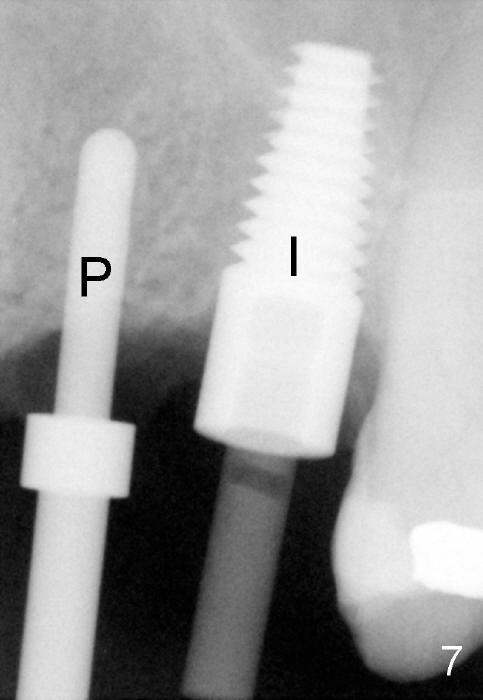

The anterior retainer is kept as a crown at #11 (Fig.2: C), whereas the residual root at the site of #13 is extracted with apical perforation (Fig.3 ^).  It is confirmed by Fig.4 (<).  To close the perforation, an osteotomy is initiated on the palatal wall of the socket with a 2 mm osteotome (Fig.5 insert: circle).  As the osteotomy is being enlarged by a 3 mm osteotome, the bone between the original socket and the osteotomy is being pushed buccally.  The former is being closed (Fig.5).  The osteotomy is finished with combination of osteotomes and reamers.  Fig.6 shows that a 5x14 mm tap is inserted at the site of #13 and that the sinus floor is lifted.  In fact the sinus membrane is partially torn at the osteotomy, which is repaired by insertion of Colla-form Dressing (Impladent), followed by autogenous bone (harvested from reamers) mixed with Osteogen  (Impladent).  A 5x14 mm implant is placed at the site of #13 with insertion torque more than 60 Ncm (Fig.7: I).  An incision is made at the site of #12 to start osteotomy with insertion of a parallel pin (Fig.7 P).  A 3 mm reamer is kept in place for position confirmation (Fig.8 R).  Due to ridge atrophy (Fig.2 arrowheads), a much smaller, but longer implant is placed at the site of #12 (Fig.9: 4x17 mm).  The autogenous bone harvested from #12 osteotomy is placed in the buccal gap of #13, followed by insertion of Colla-form Dressing (Fig.10 M).  To protect the membrane, a short abutment (4x3 mm) is temporarily placed (Fig.9,10 A) and perio dressing (Fig.9 D) is applied around the abutment and the interproximal areas of the neighboring teeth.  Usually perio dressing dislodges around 1 week postop, particularly for a large edentulous space.  In this case, the dressing is quite stable 11 days postop: the abutment (Fig.11 A) appears to contribute to retention of the dressing (D).